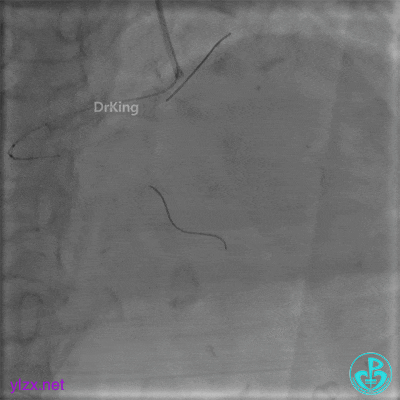

更换6F JR 4.0指引导管,Runthrough NS进入PL分支。

2.0×15mm球囊扩张PL分支开口后PL恢复2级血流。

PL远端血管周围似乎有片状造影剂滞留。

经微导管PL分支造影,该如何解读这个经微导管造影结果?

经微导管造影。